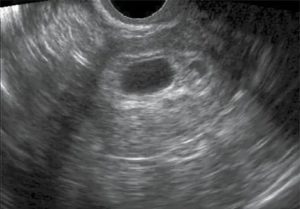

Для уточнения патологии проводится ультразвуковое исследование, на снимке визуализируются отдельные компоненты зародыша или кровяные сгустки. На развитие воспалительного процесса указывает повышенное содержание лейкоцитов при сдачи анализа мазка или крови.

Гинеколог выявляет мягкую консистенцию органа при осмотре. Подтверждают развившийся негативный процесс клинические и биохимические анализы мочи и крови, трансвагинальное УЗИ (ультразвуковое исследование).

Проводится визуальный осмотр шейки матки и пальпация. Внутренний зев ее будет расширен, плодный остаток в наличии. УЗИ определит его объем и локализацию, а также общее состояние репродуктивных органов. Биохимический анализ крови расскажет о функционировании органов и систем пациентки.